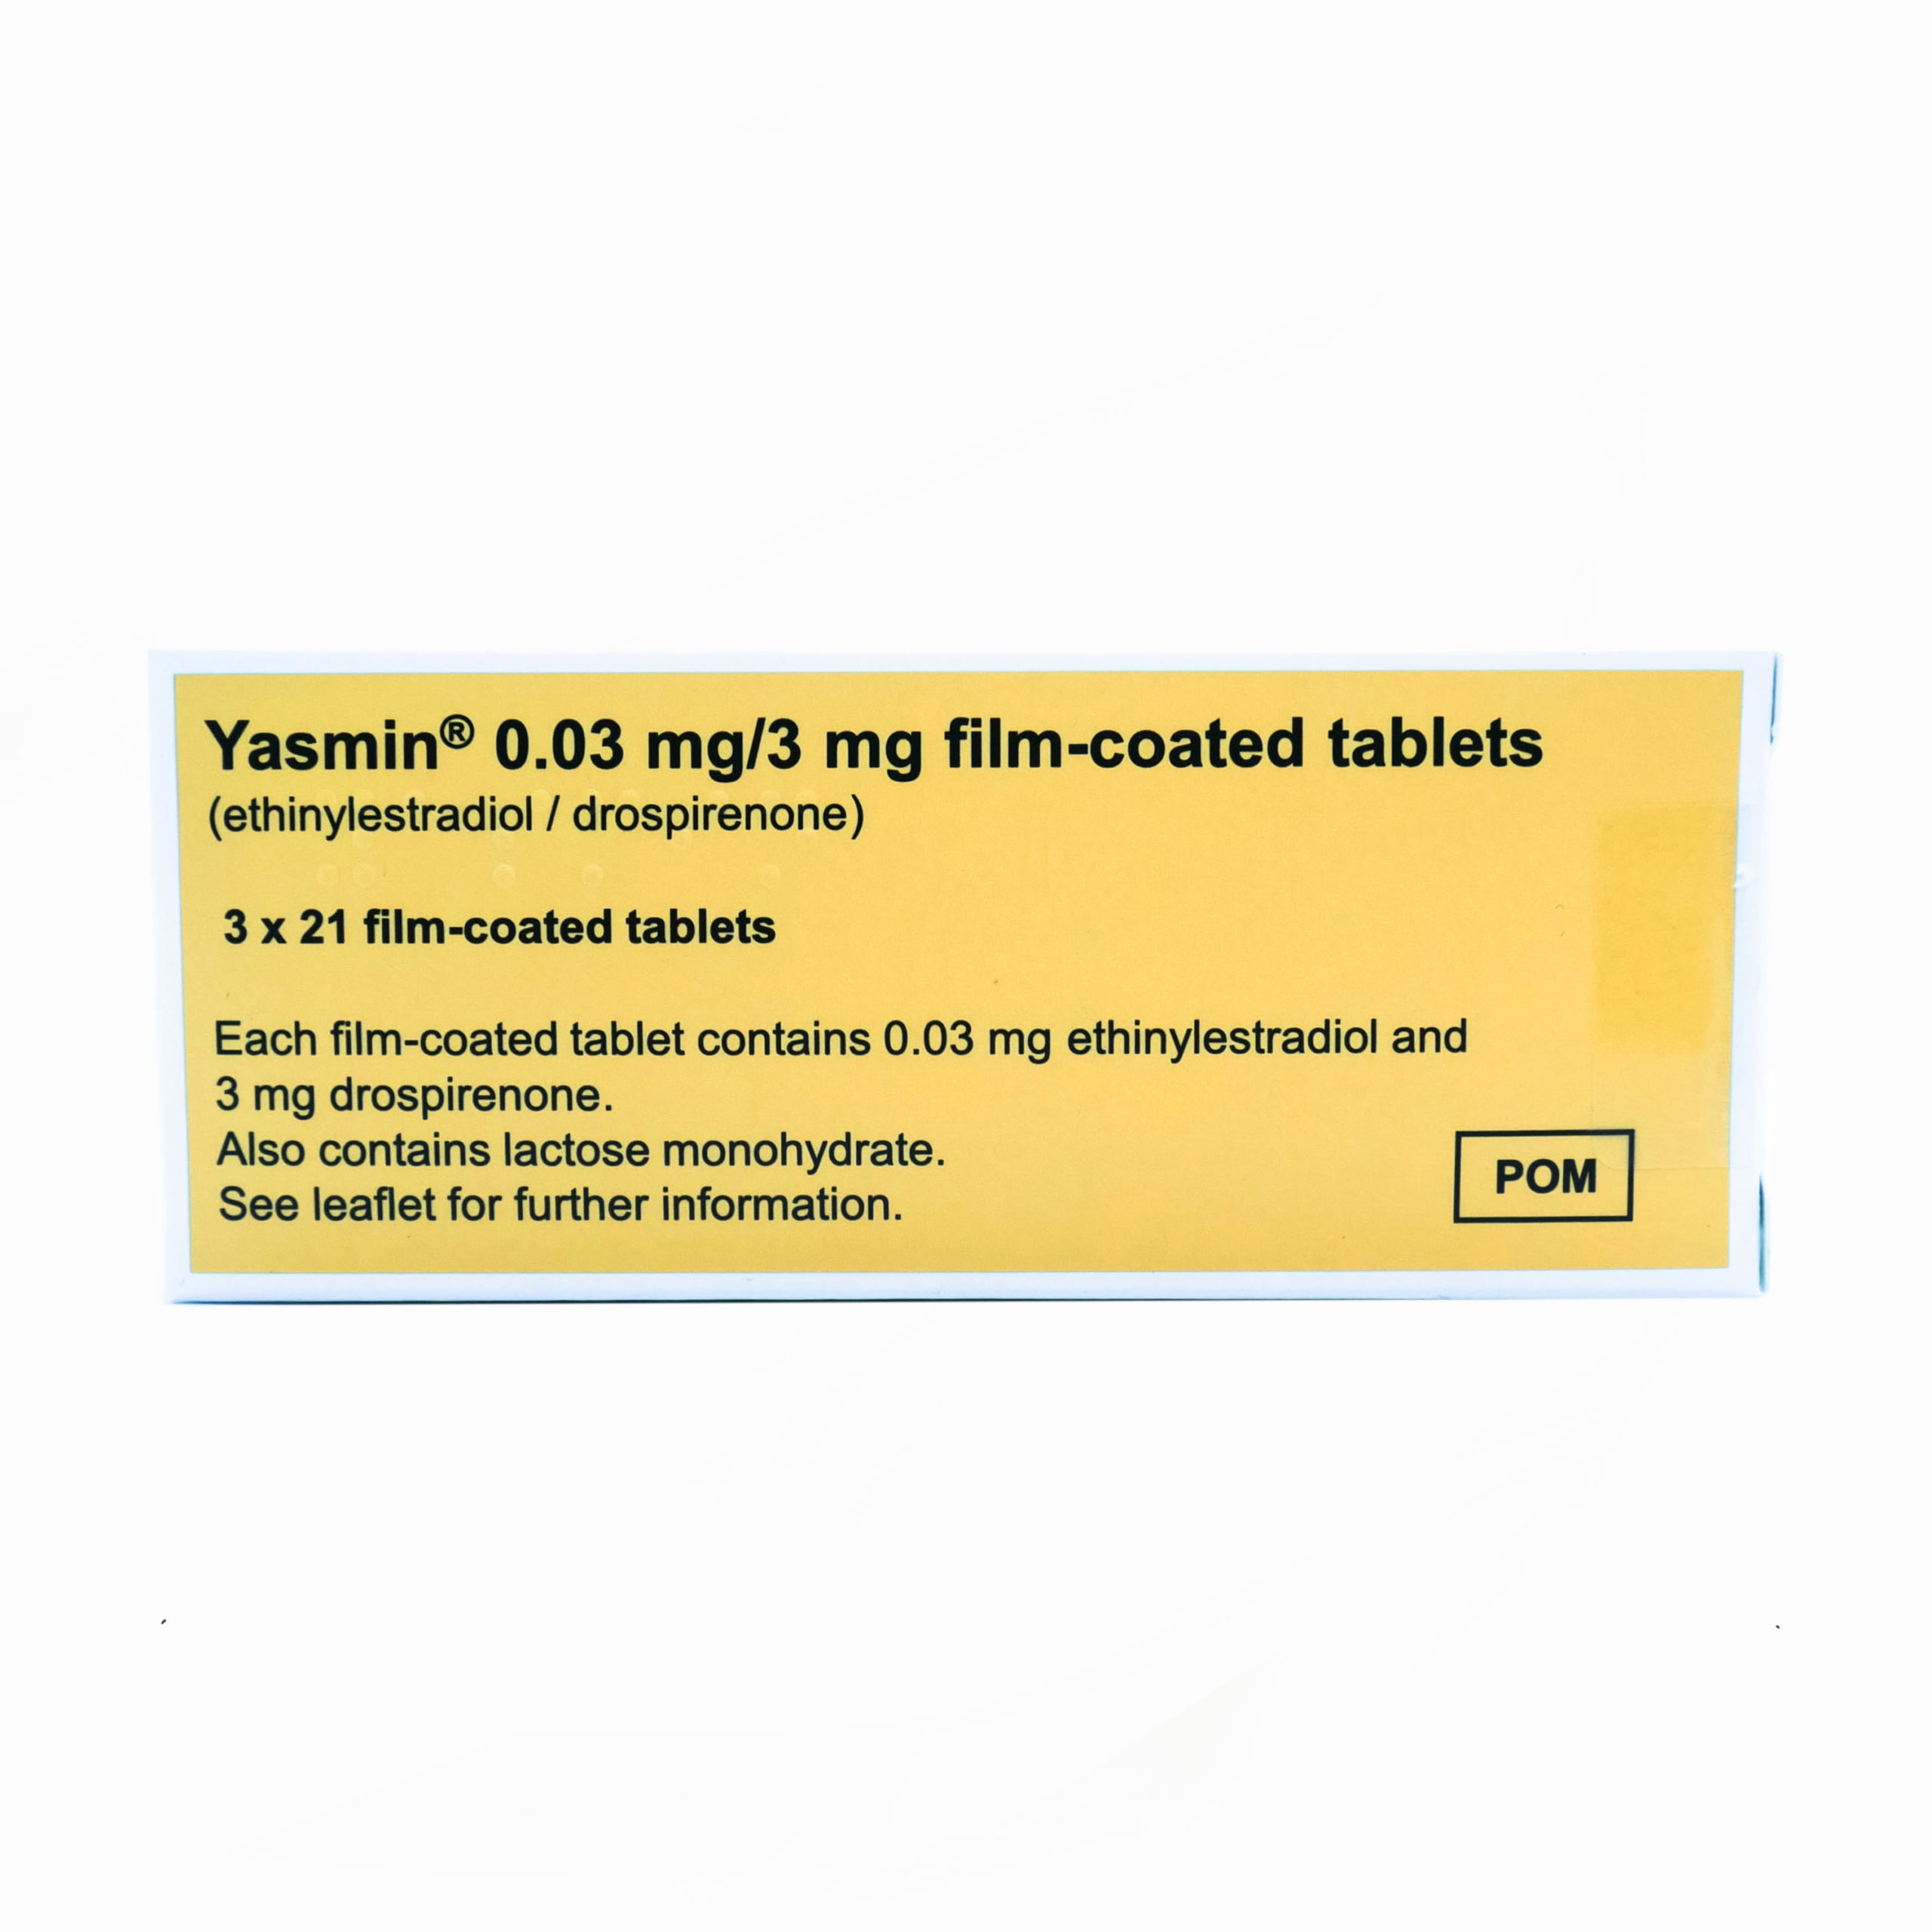

Yasmin

Yasmin is a combined oral contraceptive pill used to prevent pregnancy. It contains two active hormones: drospirenone (a progestogen) and ethinylestradiol (an oestrogen). Yasmin works by preventing the release of an egg from the ovaries (ovulation), thickening cervical mucus to make it harder for sperm to reach the egg, and thinning the lining of the uterus to prevent implantation. In addition to its use as a contraceptive, Yasmin may help regulate menstrual cycles, reduce period pain, and improve skin conditions like acne in some users.

Drospirenone and ethinylestradiol are the active components in Yasmin.

Lactose monohydrate, maize starch, pregelatinized maize starch, povidone K25, magnesium stearate (E470b), hypromellose (E464), macrogol 6000, talc (E553b), titanium dioxide (E171), iron oxide yellow are among the inactive ingredients in Yasmin (E172).